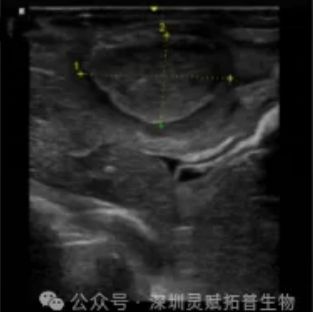

影像学监测:术后 3/7/14 天超声评估肿瘤大小(典型表现:7 天可见 10-15 mm 低回声结节)。

图 2:术后 7 天超声监测肿瘤生长影像 -